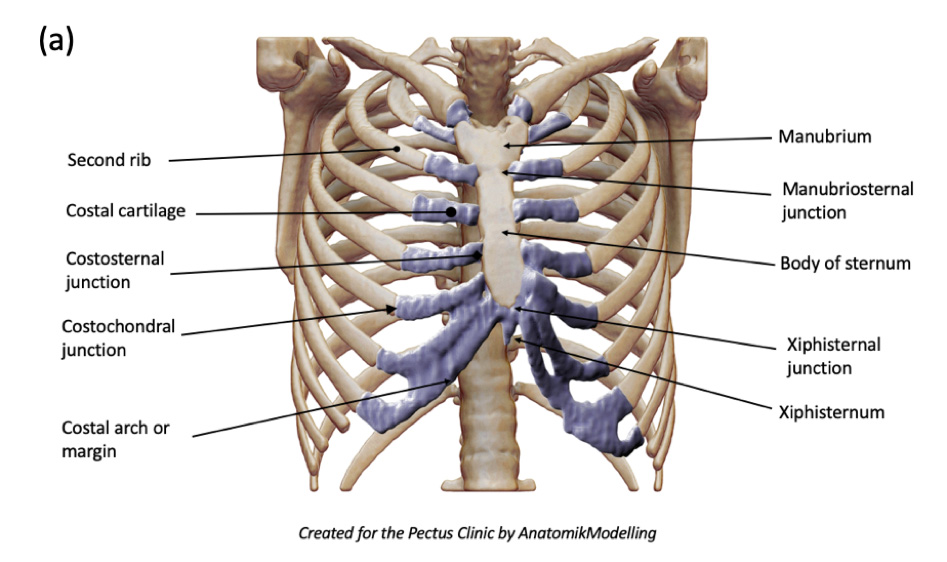

Surface Anatomy and Skeleton of the Abdominal Wall

- Key Landmarks:

- Xiphisternal junction

- Xiphoid process

- Costal margin